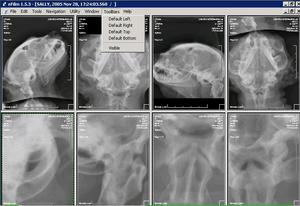

SOFTWARE: manejo de las imágenes procesándolas de múltiples formas. |

DICOM. La imagen DICOM se puede examinar de múltiples formas: ampliando, en copia negativa, realzando , etc.. Sólo se puede manejar con software DICOM. |